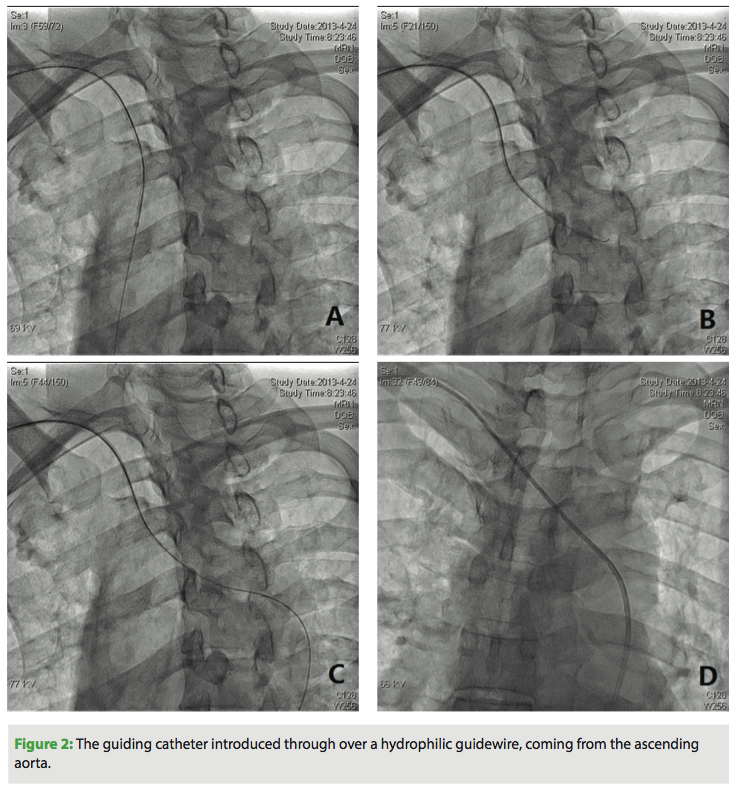

Under local anesthesia, using a modified Seldinger technique, a 6 Fr introducer sheath (Cordis Corporation) was inserted into the radial artery. A heparin bolus of 3000 units was administered intravenously and a continuous infusion of fentanyl and midazolam was started (5 µg and 0.2 mg/kg/h, respectively) and maintained until completion of RDN. In each case, the operator could easily advance a 6 Fr MPA1 guiding catheter (125 cm; Cordis Corporation) to the orifice of the renal arteries over a 0.035˝ HiWire angled hydrophilic guidewire (Cook Medical) (Figure 2). Renal angiography was first performed to further assess renal anatomy and dimensions (Figures 3A and 4A). Then, a 155 cm Iberis ablation catheter (AngioCare) was inserted and its tip was positioned proximal to the bifurcation of the renal artery. As previously described,3,4 4-8 ablations of 8 W or less and lasting up to 120 s each were performed along the length of the renal artery, separated both longitudinally and rotationally (Figures 3B, 3C, 4B, 4C). The procedure was repeated in the contralateral artery.